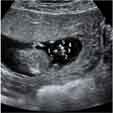

Esta ecografía en rotación muestra un embarazo gemelar de 12 semanas. La imagen en tres dimensiones muestra claramente dos fetos en sus respectivos sacos amnióticos. La membrana de separación entre ambas bolsas es bastante gruesa. Como la separación es muy clara, eso quiere decir que además de dos bolsas, existen dos placentas. Una de ellas se aprecia en la parte inferior izquierda de la cavidad uterina.